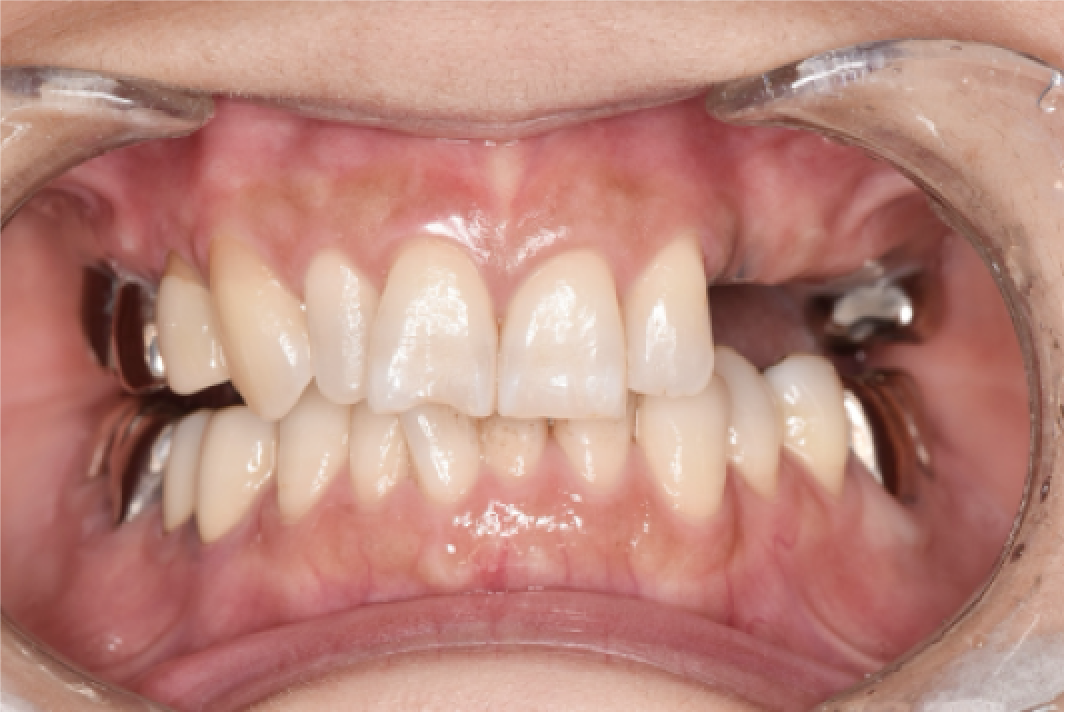

CASE04

■ 治療内容

上下顎All-on-4インプラント治療

■ 治療費用

6,627,000円(税込)

■ 治療期間

約9ヶ月

■ リスク

治療後の腫れや出血、またメンテナンスを怠ることで周囲炎のリスクあります。